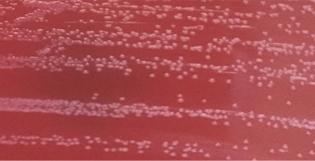

图1. 空肠弯曲菌,双孔滤膜CCDA42℃ 72h

图2. 胎儿弯曲菌血平板42℃,微需氧72h

1. 培养方法:弯曲菌生长缓慢,有正常粪便菌群存在的情况下很难分离[60]。传统培养法是先将便标本进行增菌,然后转种于选择性培养基上,在42℃的微需氧环境中孵育48-72h[20]。临床常用的选择性培养基有:改良炭头孢哌酮脱氧胆酸盐琼脂(modified cefoperazone charcoal deoxycholate agar,mCCDA)、Campy-Line琼脂、Karmali琼脂、木炭选择性培养基(charcoal selective medium,CSM)和头孢哌酮,万古霉素,两性霉素B(Campy cefoperazone, vancomycin, amphotericin B,CVA)琼脂等[61-63]。培养基之间的主要区别是抑制杂菌的抗生素类型和浓度不同[54]。一项研究对4种选择性培养基进行性能评估,认为它们分离弯曲菌的效果相当,没有显著差异[64]。膜过滤培养法已证明可提高弯曲菌检出率,但是这种方法并没有得到广泛应用[65, 66]。虽然培养法是实验室主要选择,但由于存活但不可培养(VBNC)状态细菌的存在,以及肠杆菌科其他细菌的耐药性严重,弯曲菌极易被漏检,造成假阴性结果。本实验室数据证实,中国CDC监制的双孔滤膜法在临床上获得了较好的应用数据[50]。菌落鉴定简单快速的方法是MALDI-TOF质谱,基本解决了弯曲菌的鉴别问题。鉴定明确菌落可通过MH血平板置CO2培养箱48h进行AST(抗菌药物敏感试验),判断标准采用CLSI M45。KB纸片法的药敏结果对临床有良好的指导作用。